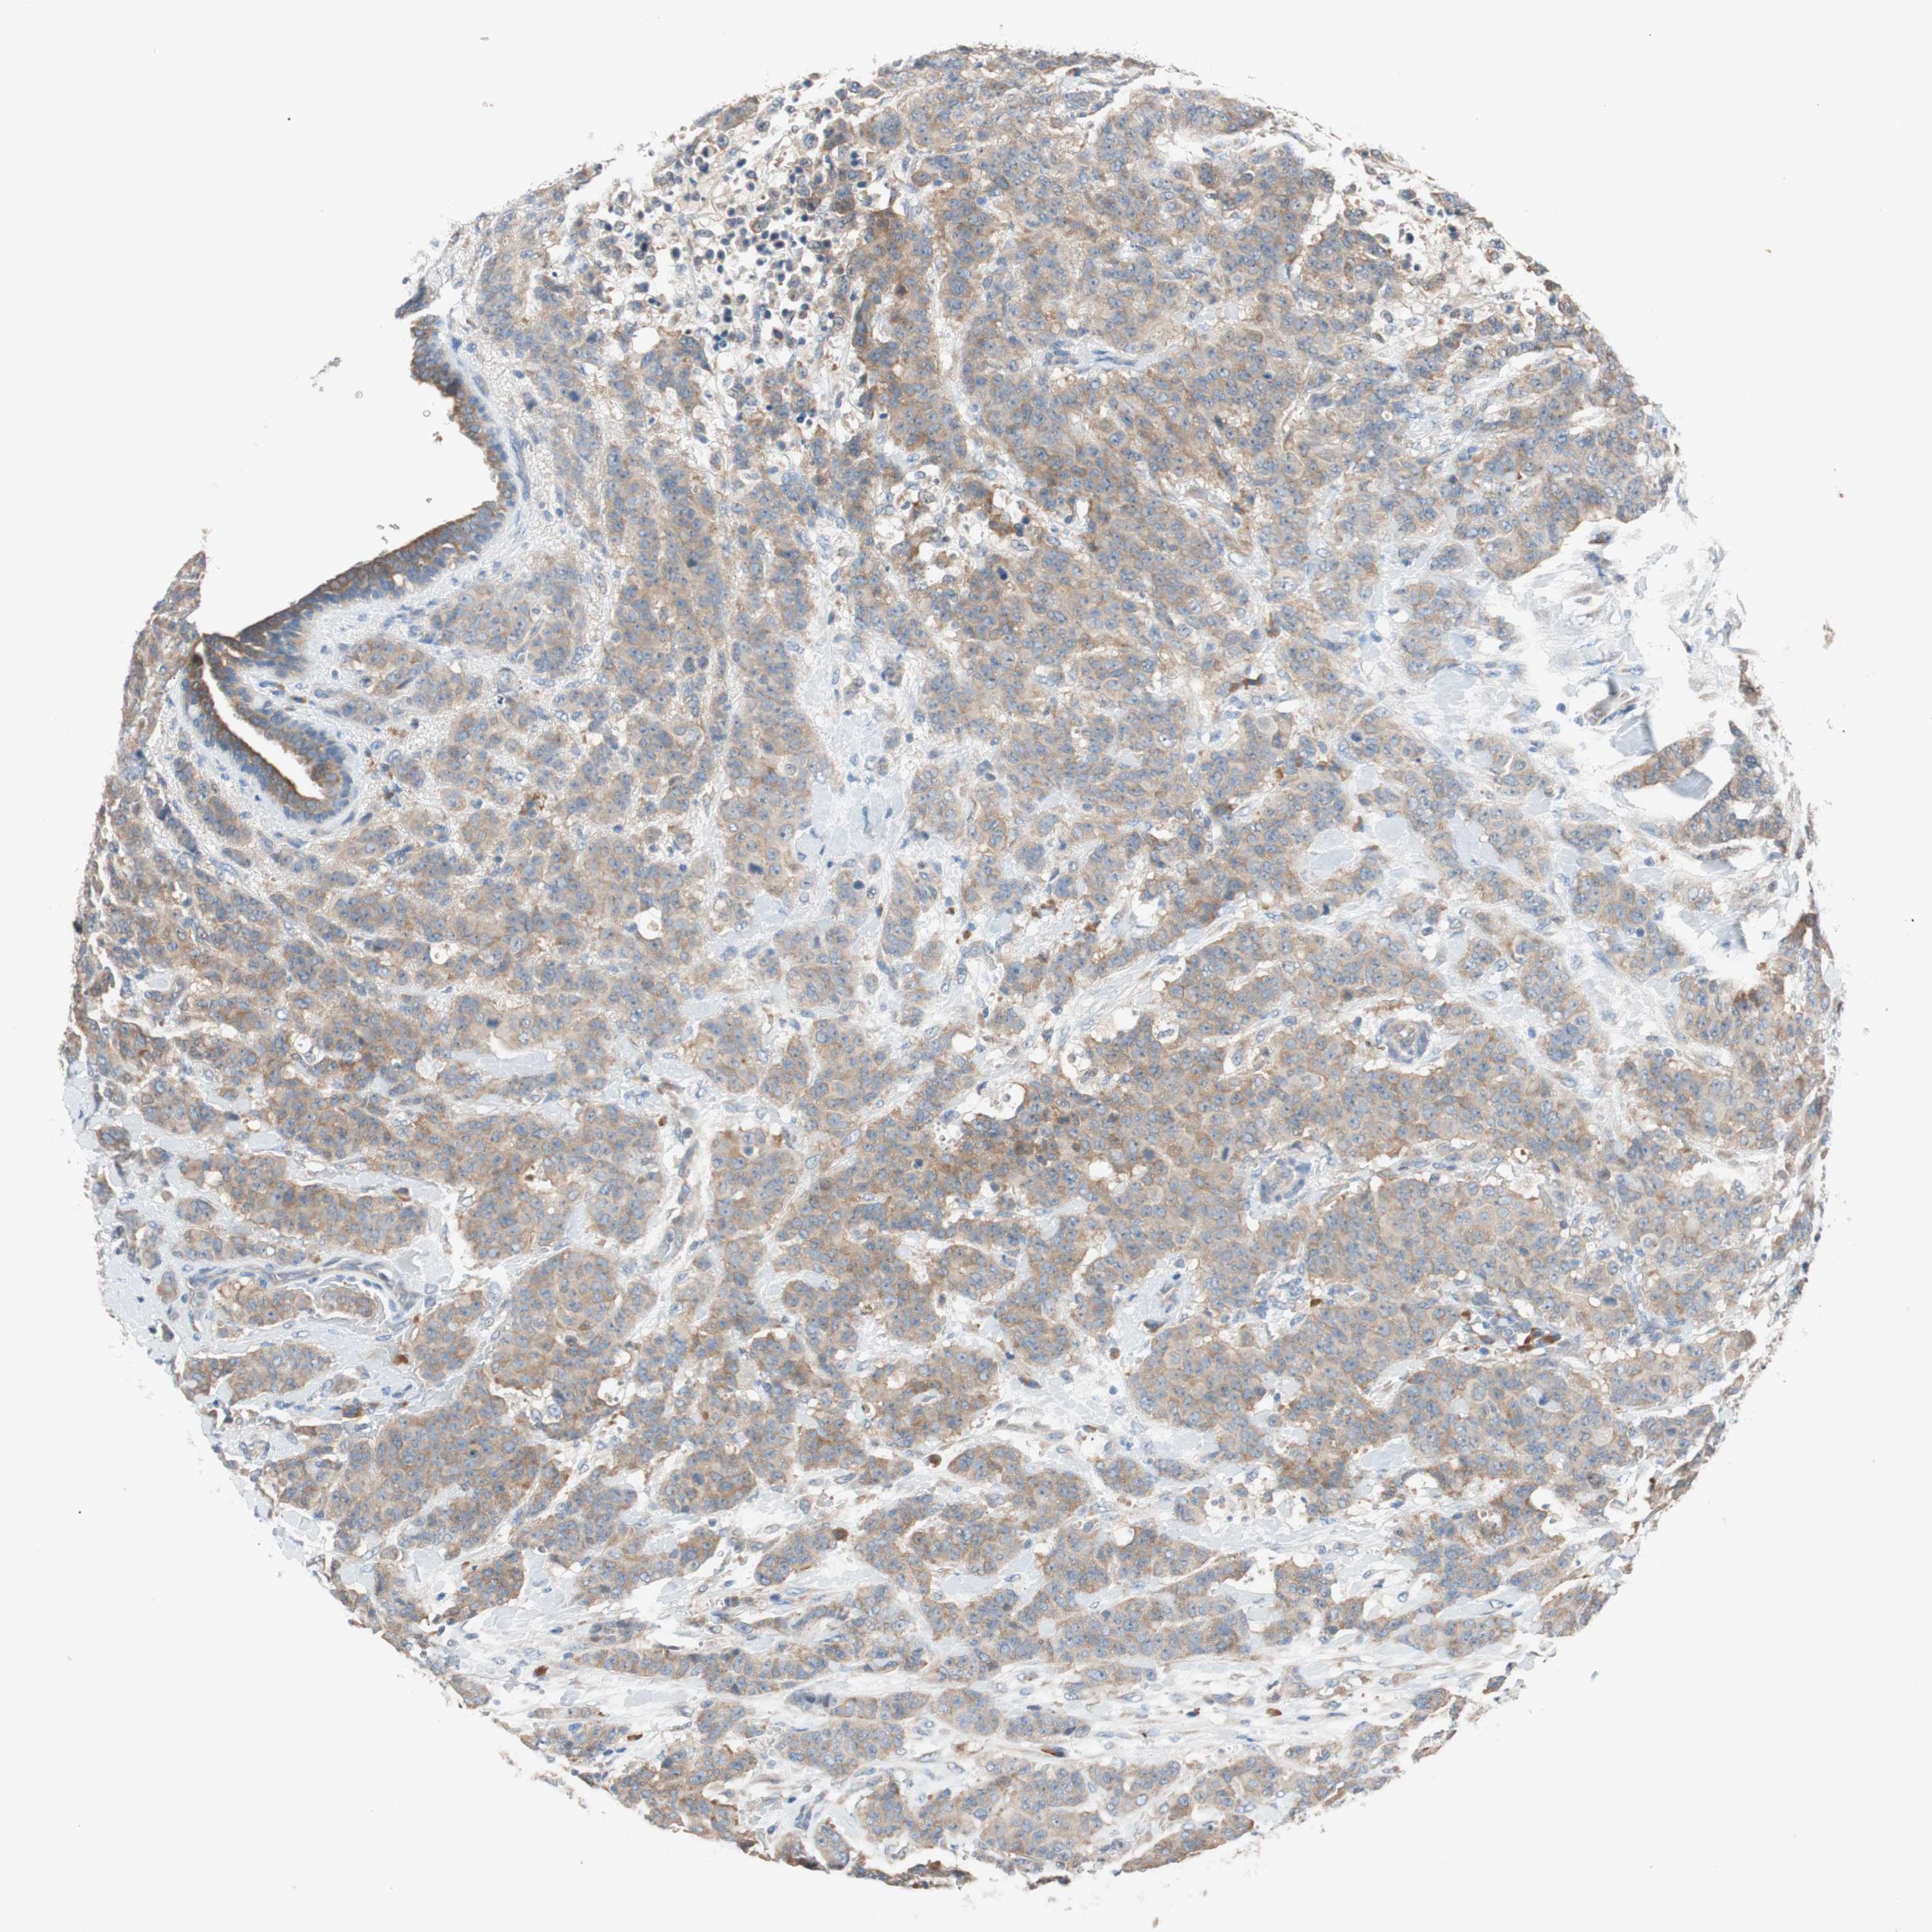

CANCER BREAST CANCER Show tissue menu

BRCA TCGA BRCA VALIDATION PROTEIN EXPRESSION